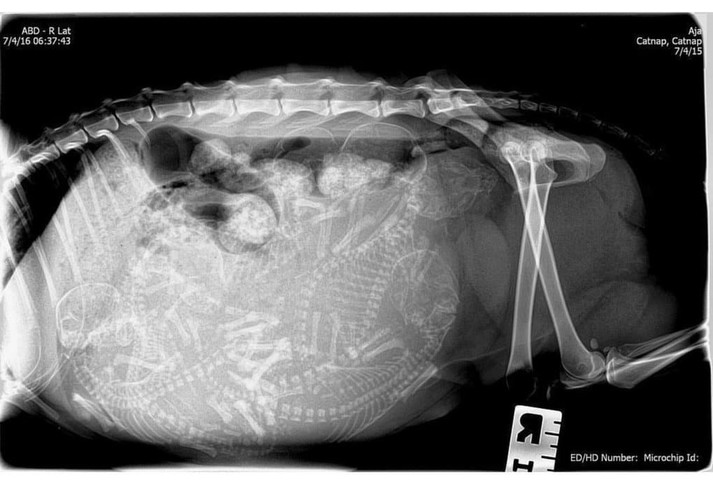

15 удивительных рентгеновских снимков беременных животных

Для женщины первое УЗИ запоминается на всю жизнь, но и рентгеновские снимки животных не менее удивительны

Но а как же выглядит беременность у братьев наших меньших?

Специалисты, которые по долгу своей работы наблюдают животных, готовых принести потомство, поделились этими удивительными рентгеновскими и ультразвуковыми снимками.